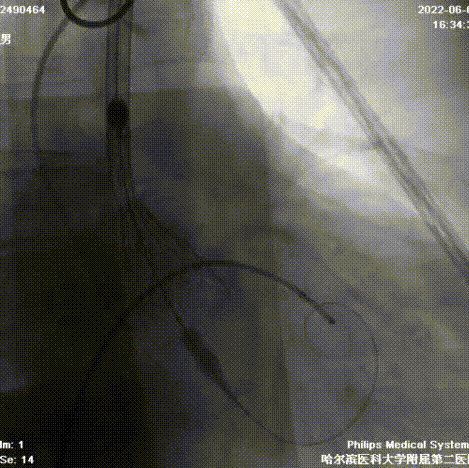

造影检查入路

根部造影

球囊预扩

首次释放

二次释放

瓣膜释放完成